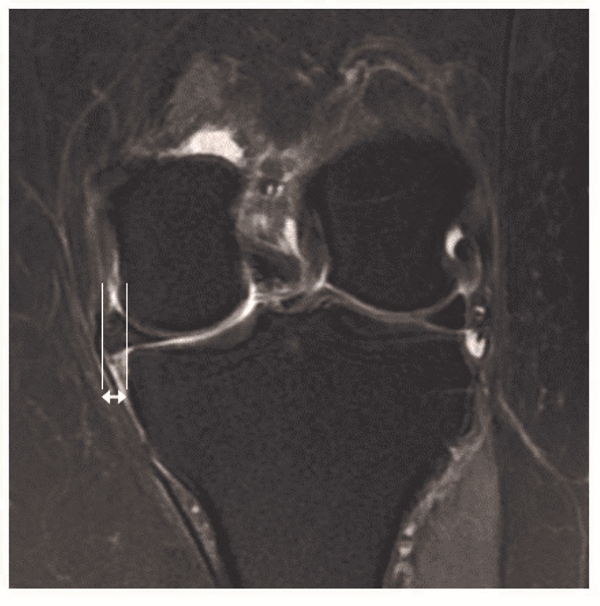

图4 MRI冠状位显示内侧半月板外突 箭头所示为半月板外突的距离

目前关于MMPRTs手术疗效评估指标主要包括了临床评估和影像学评估两方面。临床评估一般采用Lysholm评分量表、IKDC(International Knee Documentation Committee)评分量表,HHS(Hospital for Special Surgery score)评分量表以及Tegner activity score评分量表等对膝关节功能进行主观的评估,其中最常见的为Lysholm评分量表,其次为IKDC评分量表。影像学评估内容包括了MRI评估和X线评估。一般采取常规序列的MRI检查来评估半月板的愈合情况、半月板外突的情况以及软骨损伤情况。其中半月板愈合分为完全愈合(MRI三个平面上均无半月板断裂信号)、部分愈合(MRI三个平面中1个或2个平面出现半月板断裂信号)和不愈合(MRI三个平面上均出现半月板断裂信号)。内侧半月板外突是通过内侧胫骨边缘的正切垂线和内侧半月板外侧缘正切垂线之间距离进行评估(图4)。X线评估一般通过站立位正侧位或者膝关节屈曲45°位的X线片来评估患者关节间隙的狭窄情况,并进行Kellgren-Lawrence(K-L)分级,进一步评估患者骨关节炎的进展情况。